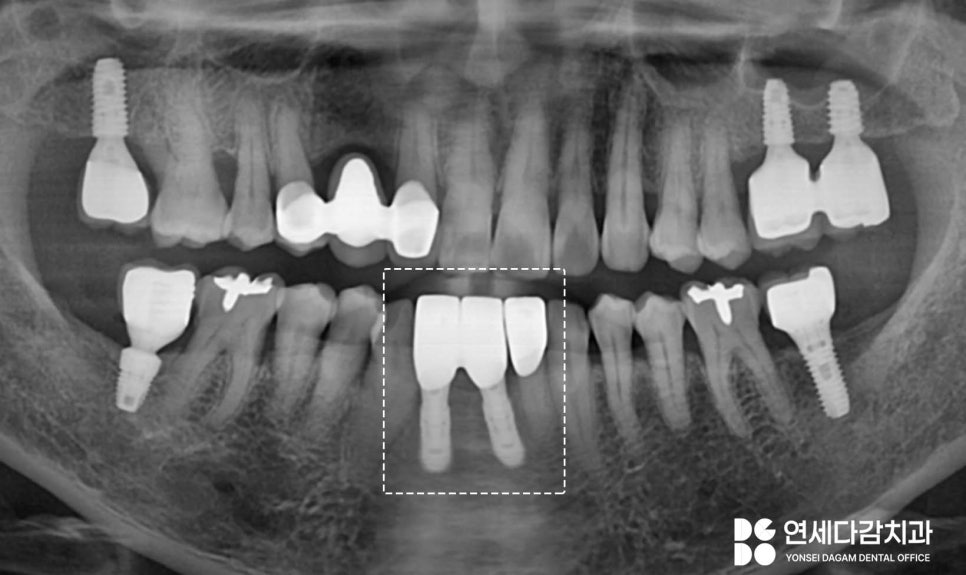

3개월간의 골 유착을 위한

치유 과정을 가졌습니다.

이 기간 동안 식립된 고정체(Fixture)와

뼈가 단단히 결합하면서

자연치와 같은 안정성을 확보하게 됩니다.

골유착이 제대로 이루어져

고정력을 갖춘것을 확인하면

보철 제작 단계에 들어가게 되는데,

기존대로라면 4개의 치관 형태가

들어가는 것이 맞으나

공간이 협소하였기에

브릿지가 아닌 임플란트 개수만큼의

보철을 제작하여

애매한 공간을

닫으려고 합니다.

위생 관리하기 더 편하고

구조적으로 안정화된 보철을 제작하여

세팅을 완료했습니다.

치료 전 지대치에만

힘이 분산됐던 구조와 달리,

이제는 안정적이고 튼튼한

구조로 개선되어 장기적인

예후를 도모하였습니다.